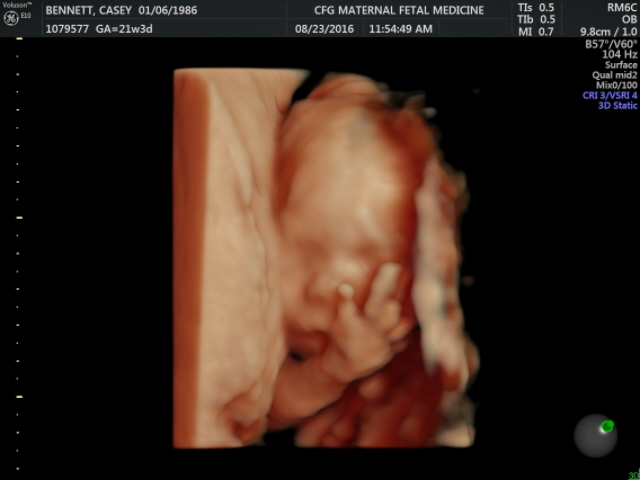

We had planned to not find out the gender this time around (and we did not find out at the initial 20 week anatomy scan), but when we learned how many more ultrasounds and tests we were in for, we dropped that idea like a hot potato. Which is a good thing, because when we went down to our ultrasound the following week in Springfield, we got a realllyyy clear between the legs shot the moment she put the monitor on my belly. Hello, baby boy! Sadly, that ultrasound did not clear up any of the confusion from the initial ultrasound (apparently they stop measuring the nuchal fold at 20 weeks and I was already 21+ weeks) and they could still see some possible thickness around the neckline. Again, the nose and the heart, ventricles, blood flow, etc. all looked really good. With that being the case, I had blood work done immediately following. It was supposed to take two weeks to come back, but I just got the call today from the genetic counselor and everything looks great (huge praise!). We were also asked to come back in three weeks for an echo-cardiogram--the reason being that if baby boy has a chromosomal abnormality, the health and function of his heart could change over time, so they would like to keep monitoring it. While the genetic test looks good, they still want to check for any heart defects--so we are keeping that appointment on the books. Lastly, they also, like my usual OBs/midwives in Corvallis, wanted to see me for a 32-week ultrasound.

On the plus side of all of these extra ultrasounds, we did get some pretty great shots of our sweet boy, Fisher Michael Bennett.